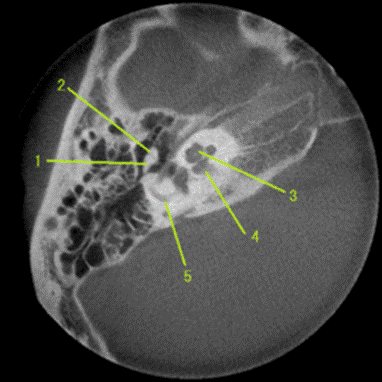

https://upload.wikimedia.org/wikipedia/commons/thumb/3/34/Malleus_and_Incus-Ice_cream_corn_sign.png/270px-Malleus_and_Incus-Ice_cream_corn_sign.png

正常な内耳のCT像、3が蝸牛に当たる。